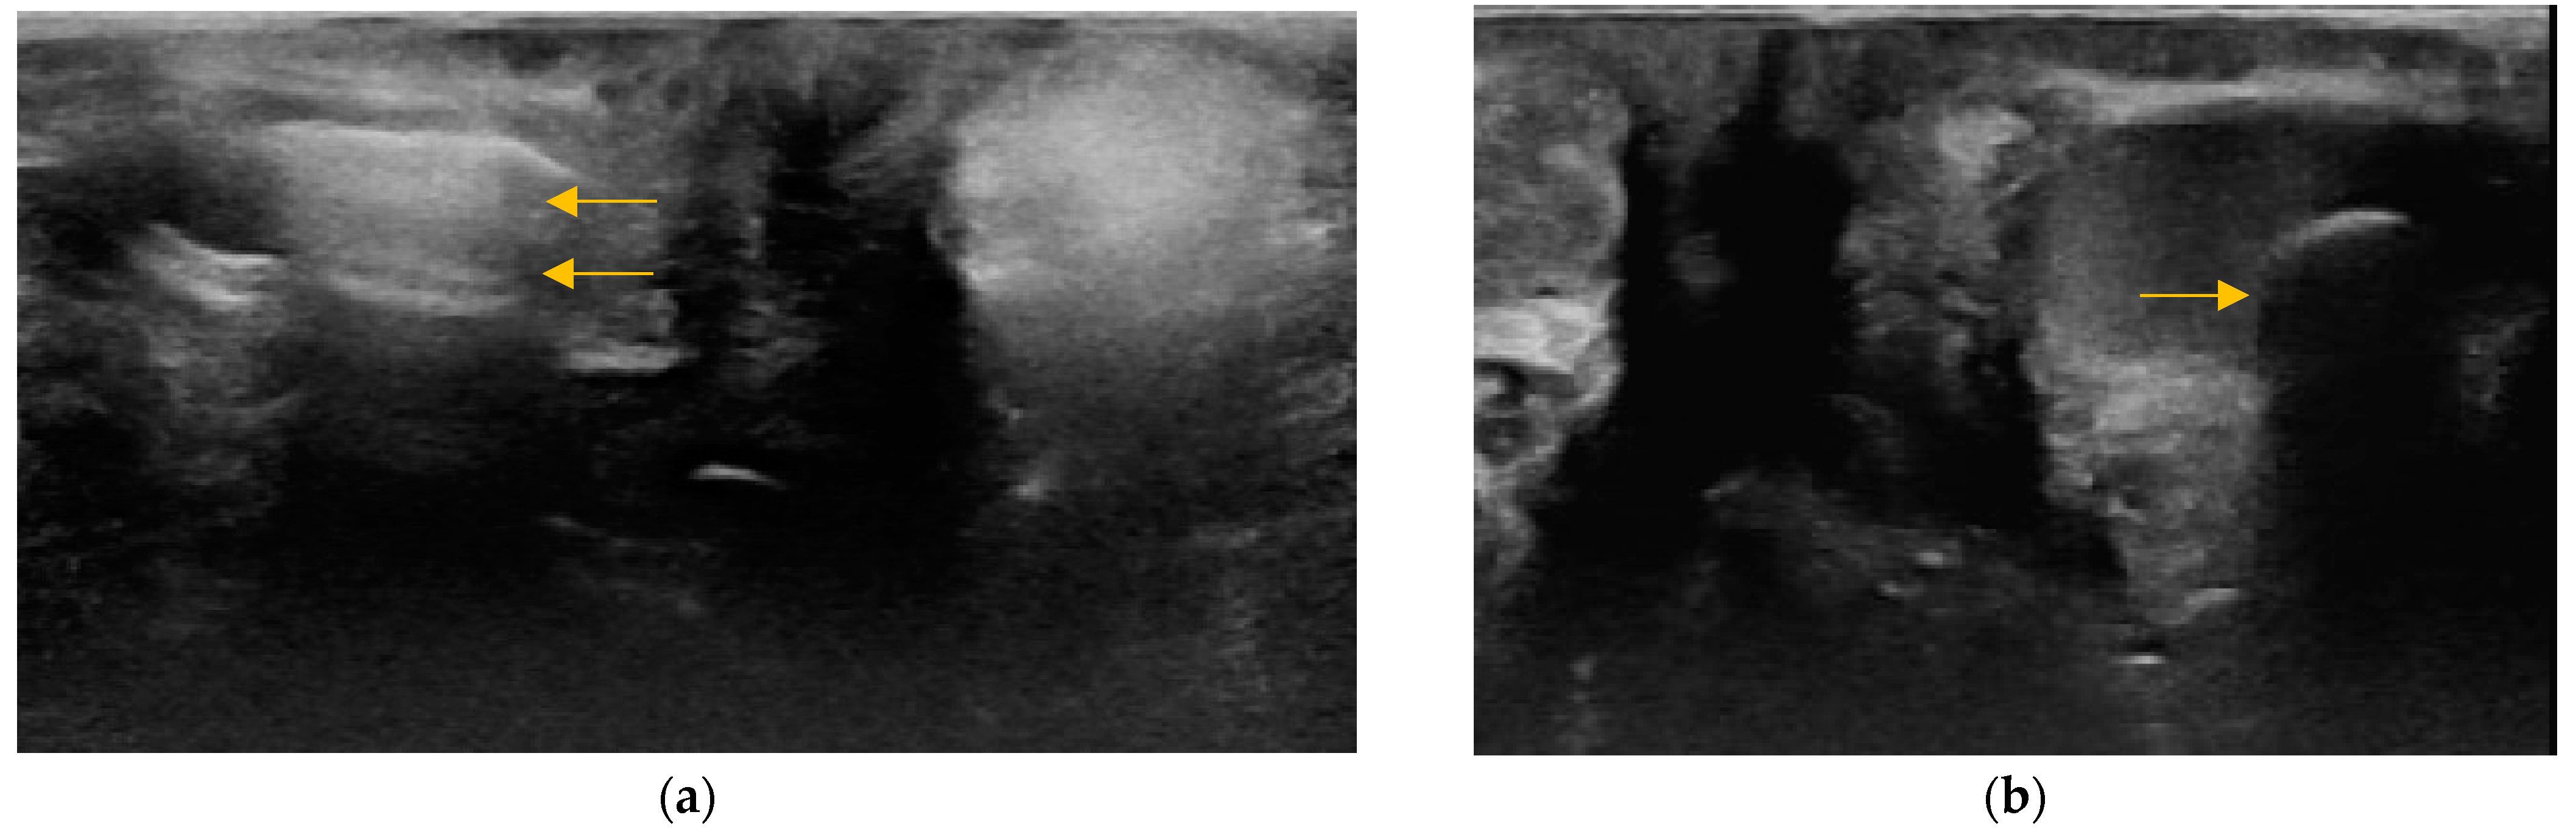

2.4.2. Size and Shape of Anal Sacs

3.3. Size and Shape of Anal Sacs

3.5. Adverse Findings